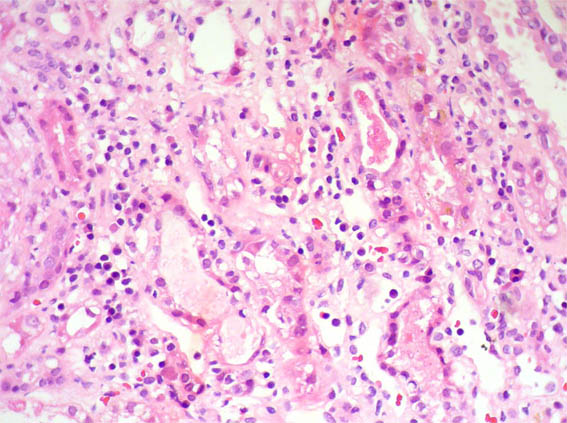

Figura 3. H&E, X400.